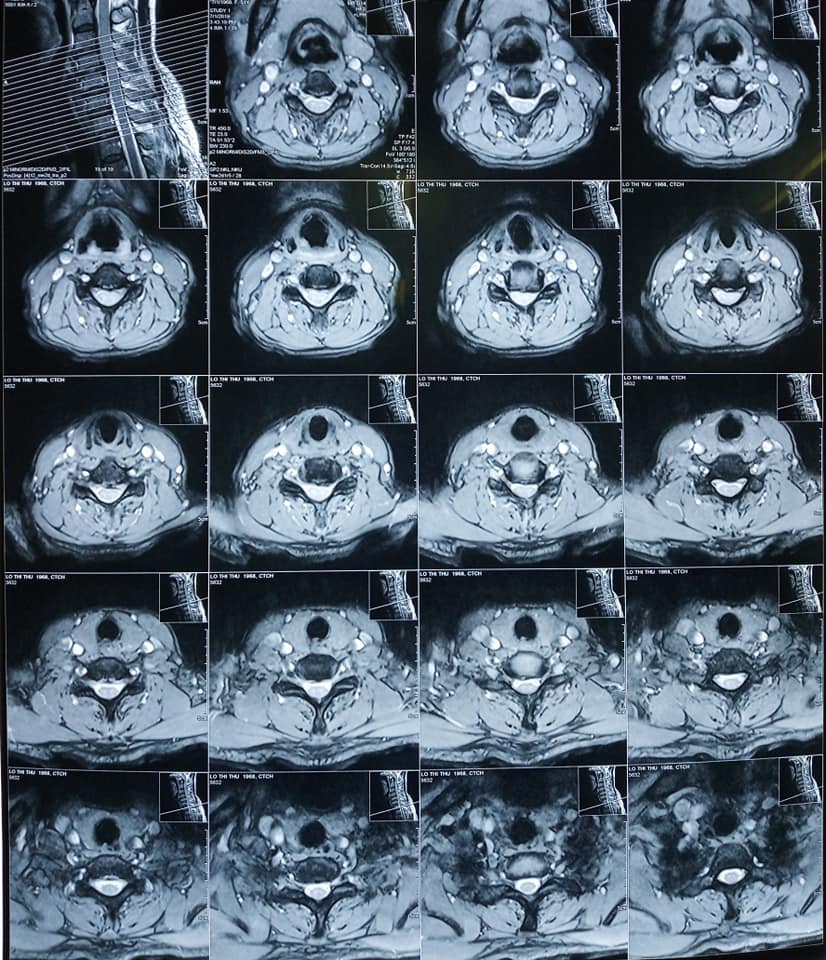

Sau khi được bác sĩ thăm khám, bệnh nhân được chẩn đoán bị Thasit vị đĩa đệm cột sống cổ C4C5 C5C6 và  phù tủy cổ ngang mức C5.

Hình ảnh Phim chụp tình trạng :